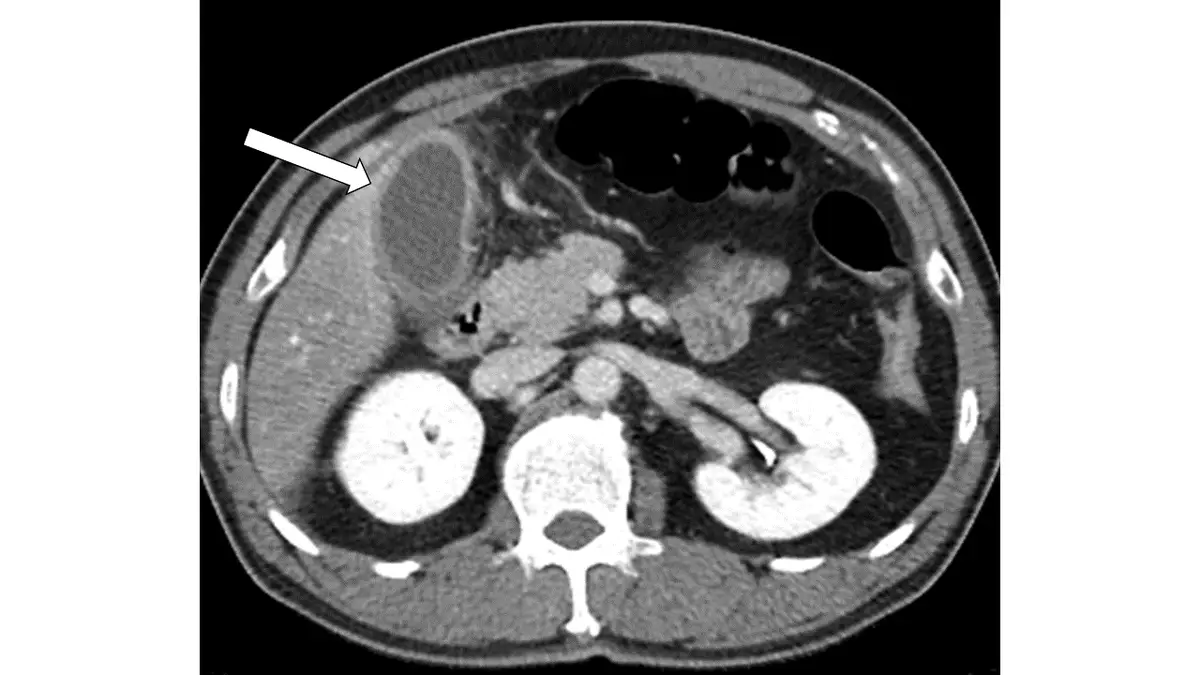

上腹疼痛病人電腦斷層攝影呈現如下圖,下列有關箭號所指那一項最正確?

本題考核上腹疼痛病人腹部電腦斷層攝影(abdominal CT)的影像判讀,重點在於辨識急性膽囊炎(acute cholecystitis)的典型 CT 表現,並與肝膿瘍(liver abscess)、胰臟炎(pancreatitis)及胃癌(gastric cancer)做鑑別診斷。

本圖為腹部 CT 軸位(axial)切面,使用靜脈注射對比劑(contrast-enhanced CT)。白色箭號位於圖片左側(影像右側,即病人右上腹),指向一個橢圓形、邊界清楚、低至中等密度的囊狀結構,位於肝臟下緣外側。

箭號所指結構:橢圓形囊狀結構,內容物密度均勻偏低(符合膽汁或稠厚膽汁的密度),壁有輕度增厚,邊緣可見對比劑強化(mucosal hyperenhancement)。

位置:結構位於肝臟(右葉)下外側,緊鄰肝臟,與膽囊的解剖位置(右上腹、肝臟床)一致。

周邊改變:膽囊周圍脂肪層密度略高(pericholecystic fat stranding),提示局部發炎反應。

其他臟器:胰臟(圖片中央稍上方)未見異常腫大或周圍積液;肝臟實質強化均勻,未見局限性低密度病灶(排除肝膿瘍);胃壁未見明顯增厚或腫塊。

整體判讀:箭號指向膨脹的膽囊